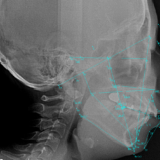

唇やほうの内側、舌の粘膜の裏側にある唾液腺から粘膜表面へ粘液(唾液)の分泌がうまく行われずに、粘膜の内側に漏れて袋状に腫れてしまうものです。

粘膜と歯が接触したり噛んだりして、唾液を分泌する管を傷つけてしまったり、けがで唇を傷つけたりして、唾液が粘膜の裏側に漏れてたまって発生するといわれています。

下唇にできて直径が5~15ミリ大の柔らかいドーム状の腫れで

粘膜の浅いところにできているものは、中身が透けて見える水ぶくれのように青紫色に見えることがあります。

深いところにある場合はやわらかいしこりになっていることがある。